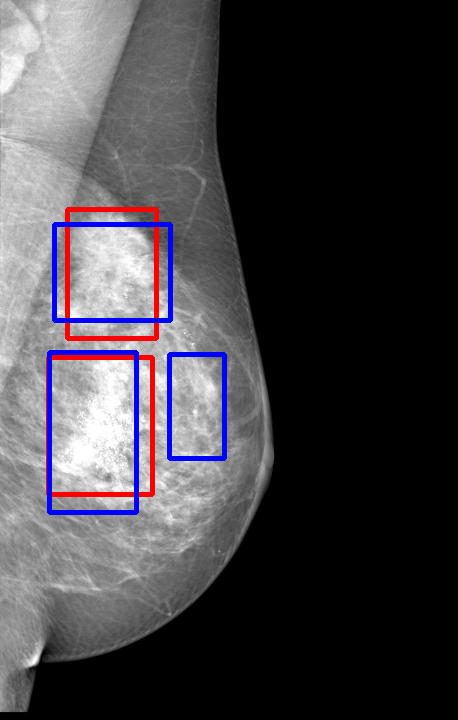

UDA has been extensively studied in case of natural images, utilizing techniques such as adversarial learning [21],pseudo-label training [6, 21, 40], image-to-image translation [40], graph reasoning [20], and adaptive mean Teacher training [6], improving domain adaptation efficiency of object detectors. Recently multiple works focused on using Mask autoencoders (MAE) methods in large-scale pretraining for vision models, involving masking parts of input and reconstructing them [12, 33]. However, these approaches overlook domain shifts. Alternatively, widespread utilization of Teacher-Student models, wherein a Teacher provides pseudo-labels for target domain (unlabeled images) to supervise a Student model, leads to notable adaptation improvements [40, 43]. However, these techniques face the challenge of incorrect predictions and excessive false positives per image due to low-quality pseudo-labels, particularly for medical imaging problems. Pseudo-labels are filtered from the Teacher model’s outputs based on the confidence score threshold. Selecting numerous pseudo-labels with low thresholds leads to inclusion of incorrect predictions, and compromising performance. Conversely, higher thresholds yield a limited number of pseudo-boxes, resulting in sub-optimal supervision. Existing Teacher-Student models often produce pseudo-labels riddled with errors and false positives, as illustrated in Fig. 1(a) and Fig. 1(b). Though [21, 40, 43] utilize techniques like adversarial alignment, weak-strong augmentation, and selective retraining of Student model to minimize the false positives in pseudo-labels, these approaches fail on medical images.

Contributions of this work. We note that screening mammography inherently differs from natural images, with breast abnormalities such as masses, asymmetries, and micro-calcifications, typically much smaller in comparison to the salient objects present in natural images, emphasizing the need for approaches specific to this problem. To address these issues, we make following contributions in this work: (1) We introduce D-MASTER, a transformer-based Domain-invariant Mask Annealed Student Teacher Autoencoder Framework for cross-domain breast cancer detection from mammograms (BCDM), integrating a novel mask-annealing technique and adaptive confidence refinement module. Unlike pretraining with mask autoencoders (MAEs) [12], leveraging massive datasets for training and then fine-tuning on smaller datasets, we present a novel learnable masking technique for the MAE branch that generates masks of different complexities, which are reconstructed by the DefDETR [44] encoder and decoder. Our approach, as a self-supervised task on target images, enables the encoder to acquire domain-invariant features and learn better target representations as shown in Fig. 1(c). (2) In Teacher-Student model, since the pseudo-label noise generated by the Teacher affects the Student model severely, we propose an adaptive confidence refinement module that progressively restricts the confidence metric for pseudo-label filtering. During the initial adaptation phase, soft confidence is applied allowing more pseudo-labels to learn better target representations. Subsequently, as confidence gradually increases, the focus shifts towards enhancing detection accuracy by prioritizing more reliable pseudo-labels. (3) We release a bounding box annotated subset of 1000 mammograms from the RSNA Breast Screening Dataset (referred to as RSNA-BSD1K) to support further research in BCDM. (4) We setup a new state-of-the-art (SOTA) in detection accuracy for UDA settings. We report a sensitivity of 0.74 on INBreast [25] and 0.51 on DDSM [18] at 0.3 FPI, compared to 0.61 and 0.44 using current SOTA respectively. Significant performance gains are also observed on our in-house and RSNA-BSD1K datasets.